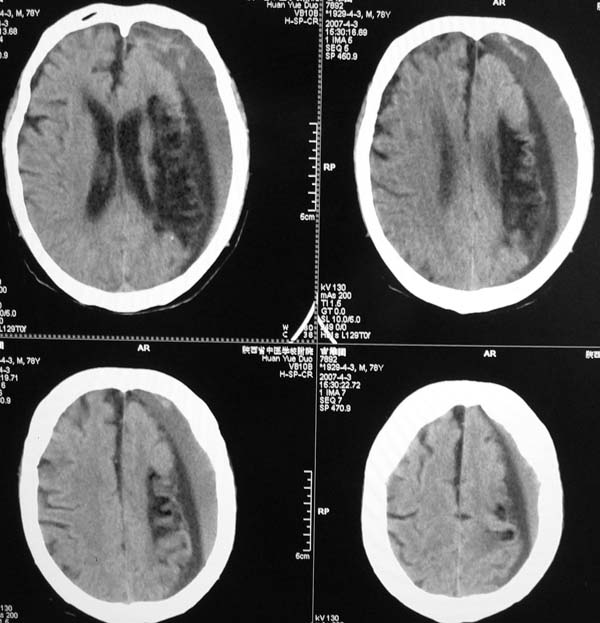

以下是引用star--868在2007-6-15 20:54:00的发言:[br]1.左侧额颞顶部亚急性硬膜下血肿并继续出血 双侧额颞顶部硬膜下积液;[br]2.左颞枕叶、左基底节区脑软化-左侧大脑中动脉栓塞;[br]双侧额颞顶部硬膜下积液应和治疗期间应用高渗脱水剂相鉴别:停用甘露醇后硬膜下积液会逐渐吸收减少,而单纯硬膜下积液无此改变和/或逐渐增多。

以下是引用狙击手在2007-6-15 21:15:00的发言:[br]软化灶就不必说了,主要是混和性血肿的渐变过程。

以下是引用老爱克斯新网客在2007-6-15 20:40:00的发言:[br]1左侧颞叶软化灶,2双侧硬膜下水瘤,3左册硬膜下血肿(多次少量出血),

以下是引用还珠格格在2007-6-16 7:07:00的发言:[br]支持.左侧额颞顶部亚急性硬膜下血肿并继续出血 双侧额颞顶部硬膜下积液;[br]2.左颞枕叶、左基底节区脑软化-左侧大脑中动脉栓塞;